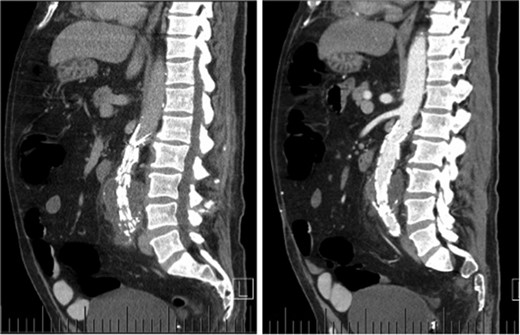

Computed tomography (CT) angiography revealed increased aortic size compared with a scan 1-month prior (5.4 cm compared with 5.0 cm) with diffuse peri-aortic inflammation. The findings implied an infected endograft (Figs 1 and 2).

Sagittal CT images indicating enlarged aneurysm sac (left) and para-aortic fat stranding (right) representing periaortitis.